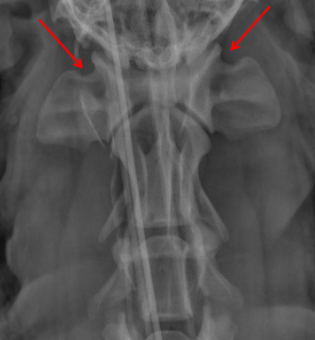

ID Radiographic View

Open Mouth VD view of Nasal Cavity

ID

Ethmoid Turbinates

Maxillary Turbinates

VOmer Bone

Palantine Foramen